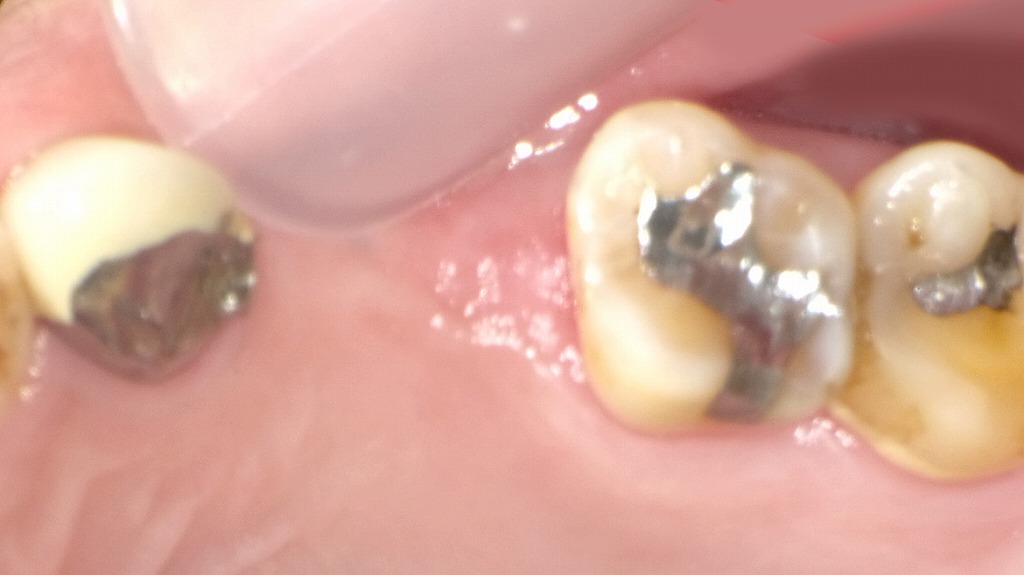

上顎4番・5番が欠損した部位に対し、インプラント治療で歯の機能回復を行った症例です。欠損状態では噛み合わせの乱れや骨吸収が進行する可能性がありますが、インプラント埋入により人工歯根を確実に固定し、周囲の歯を削らずに本来の噛む力を取り戻すことができます。術中写真では、適切な位置に埋入されたインプラント体が確認でき、今後は骨と結合することで安定した土台となり、最終的な被せ物で自然な咬合と見た目を回復していきます。